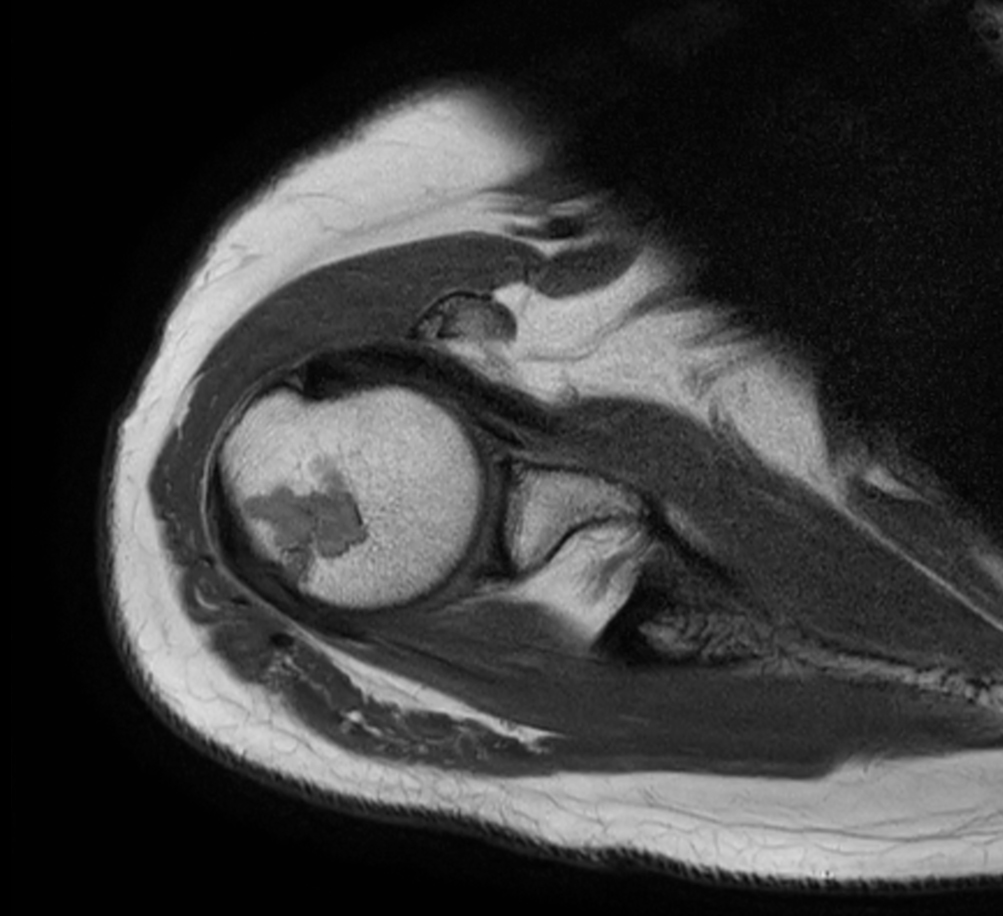

Comprehensive shoulder on BlueSeal magnet

Spital Uster, Switzerland

Axial T1w TSE